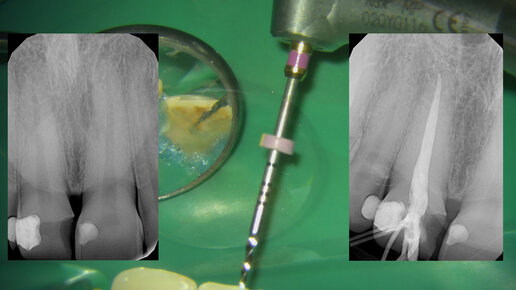

Депульпирование центрального резца